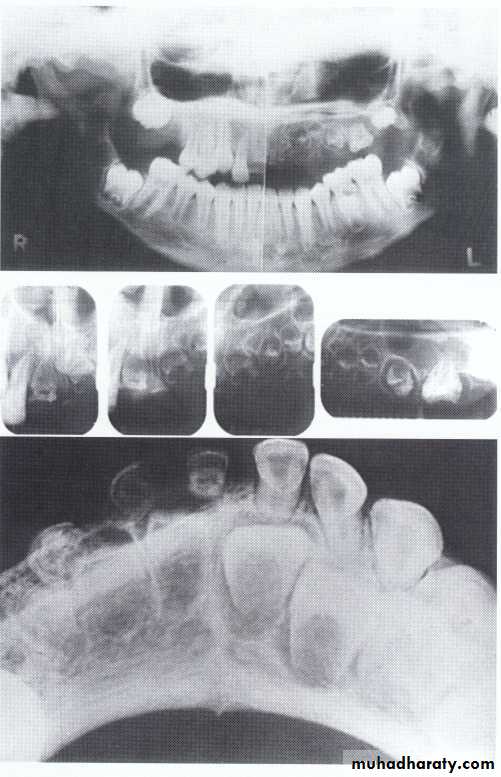

Dentin dysplasia, type I. panoramic & periapical films of the same case show the short and poorly developed roots, obliterated pulp chambers and root canals, and periapical inflammatory lesions.

Color of primary dentition is opalescent

Radiographically:

Deciduous teeth:

roots are extremely short

pulps almost completely obliterated

Permanent teeth:

abnormally large pulp chambers in coronal portion of tooth.

Type II (Coronal Type)

Dentin dysplasia, type II. panoramic &periapical films of the same case show obliteration of the pulp chamber, reduction in the caliber of root canals, and pulp stones obscuring the flame-shaped pulp chambers.

Periapical inflammatory lesions are associated with some of the mandibular anterior teeth.